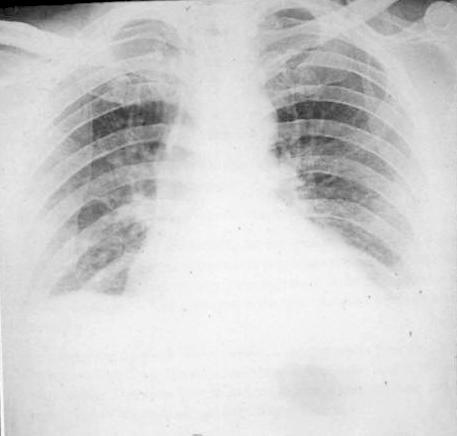

Tuberculosis

TBC signs:

1. Reticulo - Nodular

2. Apical + Parahilar

3. Uni- og Bilateral |